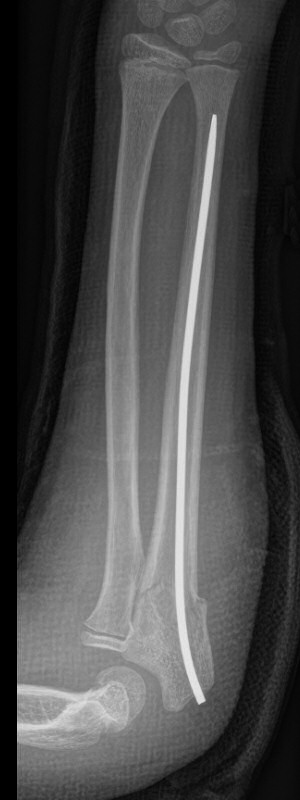

Monteggiafraktur, opererad med TEN-spik